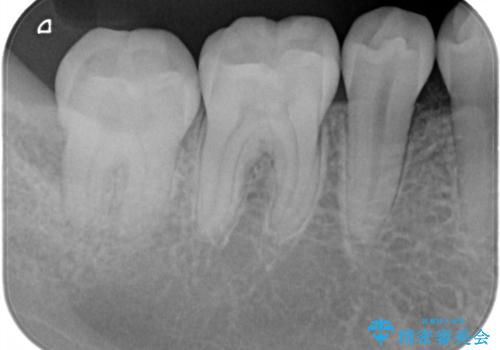

患者様は、他院で右下の歯を抜歯かもと言われました。全体の歯周病はなく、右下の1歯だけ骨が極端に減少していました(初診時歯周ポケット7mm。通常は3mm以下。)。その歯だけ咬合が強いことが原因と考えられたため、咬合を弱くする処置と減少した骨を再生する処置が必要になりました。

骨の再生治療手術をして10か月経過観察をしたのち、骨を平坦化する手術を行い、治療終了となりました。